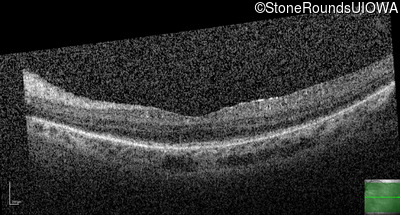

Optical Coherence Tomography - Right - 20/40 -2

Exemplar / OCT Stack